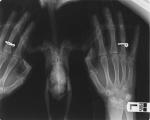

dasha105 Опубликовано 19 августа, 2013 Автор #20 Опубликовано 19 августа, 2013 А что за врач такой универсальный? Рекомендованные на форуме врачи, они что говорят, Вы же вроде не к одному вету обращались за помощью? Врач хороший, с большим опытом. И я в ,общем-то, склонна с ней согласиться. Так как я работала в приюте для кошек и собак. где скученность, там действительно жуткие устойчивые инфекции ко всему. Однако, сегодня была у другого врача и она привела мне убедительный пример, как в голубятнях сальмонеллы ( вроде до этого нелеченные) имеют естественную резистентность ко всем применяемым антибиотикам. Хотя, все мы знаем как в голубятнях лечат сальмонеллез - загрузят байтрил 10% всем в поилку и кто выпьет, кто нет... Не индивидуально каждому, а кое-как. Вот так и формируется резистентность. Также и байкокс разливают. Кому попало - хорошо, кому не попало - ничего страшного.. dasha105, есть анализы, сделанные перед отдачей на передержку? Безусловно, вы правы. Анализы не сдавала, заранее ничего утверждать не могу. Но значит и другие птицы едут на передержку без анализов. Такие же подобрыши. А в инкубационном периоде ли они, являются ли носителями, выделителями в принципе, никто и не знает. Ведь если нет внешних признаков инфекции, пока, это ничего не значит.Кстати, сдала ему анализы на сальмонеллез, орнитоз, простейшие - отрицательно. Сдала в другой лаборатории ( не шанс био) оказался кокцидиоз ( аж четыре креста между прочим!)и единичные амебы. Вот и верь анализам после этого. Вы не можете утверждать, что заражение произошло у форумчанки. Для этого требуются документы, показывающие, что до передержки заражения не было. Поэтому название темы исправлено Администратор Просто так совпало. Уехал с несерьезным переломом, активный и здоровый. А вернулся истощенным на грани смерти. Врачи удивляются, как он жив вообще. Никаких претензий к передержке нет. Но пока пожалела, что отдала. Родственники настояли на отдаче, человек мне помог. Но никого не хочу обвинять. Может и был уже больной, что-то начиналось. А может и не был. Кто теперь знает. Так, супракс в суспензии 100мг/5 мл. Так, значит в инструкции, по-моему, следует добавить 40 мл воды, проверьте меня, если что, Вы целях экономии, высыпаете содержимое флакона на белый лист бумаги, делите на 4 равные части, 3 части ссыпаете обратно во флакон, а оставшуюся 1/4 часть супракса высыпаете в рюмочку и вливаете 1/4 часть от дозировки указанной в инструкции, т.е. если все количество рекоммендуют развести в 40 мл воды, то 1/4 часть Вы разводите в 10 мл, соответственно. Хорошо перемешиваете до получения однородной суспензии и даете птицуну по 0.4 мл 2 раза в день. Полученную суспензию храните на боковой полочке холодильника 5 дней, затем готовите следующую порцию. Прикрытие пимафуцином и карсилом.Супракс - один из препаратов выбора в данном случае, хорошо работыющий. Касательно гематомы - в обязательном порядке примочки из малавита по 15-20 минут 2 раза в день. Марина, очень рада, что вы зашли. Сегодня вечером уже была у врача и мы задались вопросом, а эта энтеробактерия , не нормальное ли ее количество для птиц? Ведь анализы в расчете на млеков делают? Посмотрите пожалуйста анализ. Может для птиц он вообще нормальный? Очень долго с врачом думали и вроде сошлись на том, что антибиотики несколько дней не пьем ( пьем энтерол, где бактерии естественные антагонисты) и смотрим. Если хуже начинаем супракс. Птица крошечная, тощая, нахрен уже совсем залеченная ( 10 дней в\м байтрила - колола в\м без разведения, обошлось без некрозов, потом сменили на цефалексин - к нему все устойчиво, и два дня ципрофлоксацина, которым я птицу изуродовала. Да еще в спинку уколы по 5 мл два раза в день для регидратации, тоже гематому на спине сделала..) Жуть , в общем. Иногда залечить можно страшнее, чем не лечить. dasha105, бактерии рода Enterobacter spp сами по себе очень устойчивые перед многими антибиотиками, и у вас в анализе указано перед какими антибиотиками и насколько они устойчивы. По анализу я поняла что у гули проблемы с жкт и подозрение на микоплазмоз? На гельминты гульку проверяли? Опишите его состояние и помет. Хрипы, запах. Проблемы с жкт были - лейкоцитоз, слущенный эпителий, проблемы с поджелудочной по анализам. А потом и кокцидии еще ( с третьего раза анализ только показал). С байкоксом я уже отлично управляюсь. Через три дня никаких кокцидий. Анализ нормализовался. остались единичные цисты амеб. А помет - вода осталась Оказалась кака нормальная, а вокруг лужа. Теперь думаем на почки...Что бы подтвердить теорию о почках надо брать кровь. Врач в таком состоянии не решается это делать. Хотя еще раз приложу рентген - по нему поставили воспаление кишечника( контрасность повышена) и странное образование внизу живота ( что это не знаем, видно через кожу, прощупывается овальное). Биопсию никто в таком состоянии брать не решается. Кстати, орнитолог, рекомендуемый на форуме как один из самых лучших, на снимке ничего не заметил. Я когда стала сама смотреть , заметила опухоль и сразу побежала к другому врачу, мы опухоль прощупали.